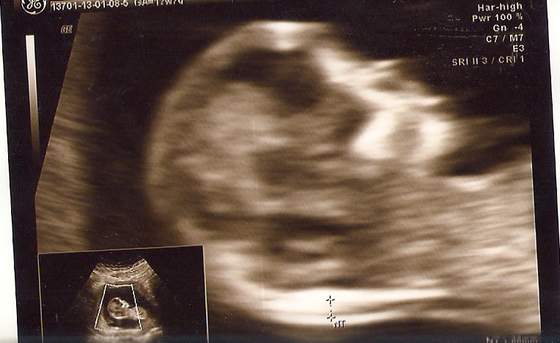

love - ja DOPIERO na 14:30 (ale i tak capnęłam pierwszy numerek, bo lekarz przyjmuje właśnie od tej godziny). Chciałabym, żeby mąż mój w końcu zobaczył i uwierzył

Ale godzina taka, że nie wiadomo czy uda mu się wyrwać z roboty, szczególnie, że następnego dnia mamy sprawę w sądzie i wziął wolne... eh...